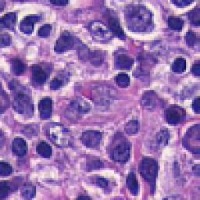

Medical Diagnostics & Research: Researchers and healthcare providers can use LDANN-BASIC to assist in the identification of lymphocyte classes, helping to diagnose diseases like leukemia or lymphoma more efficiently and enhancing our understanding of the immune system.

Pharmaceutical Development & Drug Testing: The model can be employed in pharmaceutical labs to study the effects of new drugs on lymphocyte populations, contributing to the development of more effective medications or therapies targeting specific immune conditions.

Automated Clinical Laboratory Systems: LDANN-BASIC can be integrated into automated image analysis workflows within clinical laboratories, streamlining the process of analyzing patient samples and reducing the risk of human error in lymphocyte classification.

Educational Purposes: The model can serve as a teaching tool for medical students, clinical laboratory scientists, and immunology researchers to learn and visually understand different types of lymphocytes, thereby improving their skills and knowledge in the field of histology and pathology.

Remote and Telemedicine Diagnostics: LDANN-BASIC can be used in remote healthcare settings or telemedical diagnostic systems, enabling healthcare professionals to analyze blood samples from patients even if they are located in rural or remote areas with limited access to specialized labs.